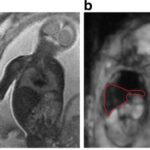

Magnetisation transfer as a biomarker for chronic airway fibrosis

This study aims to evaluate magnetisation transfer (MT) as a biomarker of developing chronic airway fibrosis (CAF) of lung transplants in a mouse model. By performing lung transplantation in 48 mice, applying major or minor histocompatibility mismatches between...